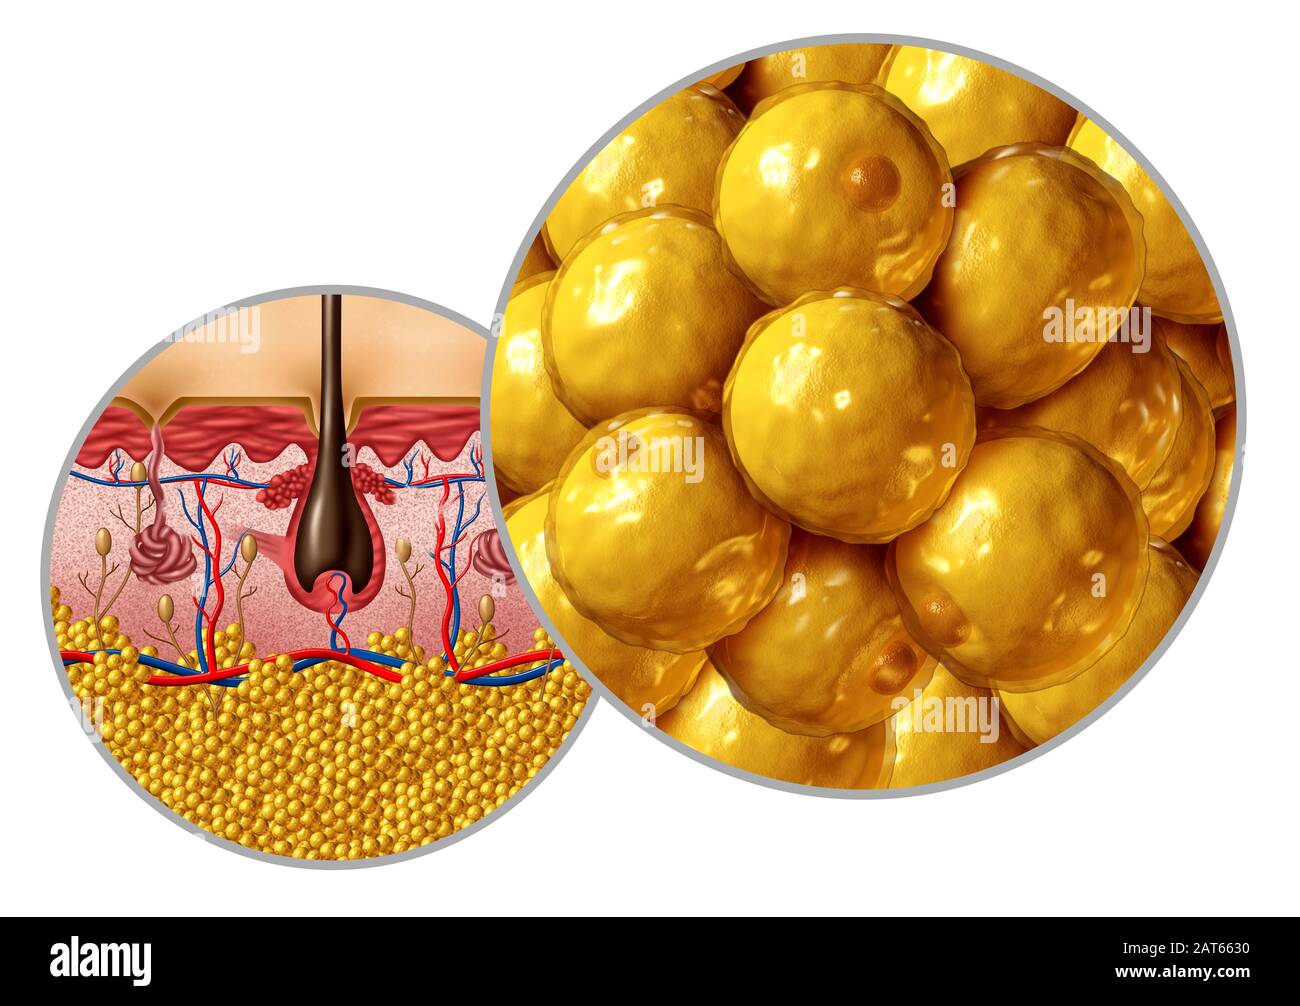

RF3A3FDTG–Diagramma microscopico delle cellule adipocite marroni con nucleo mitocondriale e trigliceridi come concetto di diagramma anatomico isolato su sfondo bianco

RFK5A7XP–Cella di grasso, illustrazione. La maggior parte di un adipocita (fat cell) è riempita con una gocciolina di lipidi (giallo). Il nucleo cellulare è rosso. Gli adipociti formare tessuto adiposo, che immagazzina energia come uno strato isolante di grasso.

RF2ARXF3B–Cellule grasse adipocyte o anatomia lipocyte come cellula umana microscopica interna per la conservazione di grassi.

RF2AT6630–Diagramma di anatomia grassa adipocita o concetto di lipocita con una sezione trasversale dell'organo di superficie del corpo umano come un'assistenza sanitaria e simbolo medico.